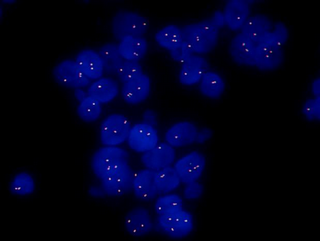

MF43-N+MSX11拍摄的FISH图片

FISH样品在紫外激发光的照射在,显现出蓝色的细胞轮廓的信号,在蓝色激发光的照射下在细胞内显现出绿色的探针信号,在绿色激发光的照射下在细胞内显现出红色的探针信号。

选择细胞核边界完整、无重叠,标记的红色信号和标记的绿色信号清晰的细胞,随机计数至少20个细胞核中双色信号。判断信号点有无分离或者有无扩增等,并在专业的病理医师或技术人员的指导下对结果进行判读,保证结果的准确性。明美研究级正置荧光显微镜MF43-N采用优良的无限远光学系统,搭配四通道光源MG-120,荧光激发信号强,并且可以即开即用,可以选配单通或双通荧光激发块,可供选择的荧光波段繁多且亮度高,可满足FISH领域的研究需要,也应用于生物制药,医学检测、疾病预防等领域内的荧光检测。